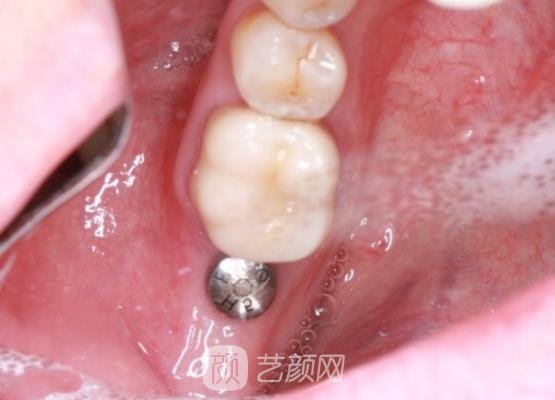

种植牙案例:

刚见到医生的时候,医生先是跟我交流了一些种植牙技术方面的问题,又让我看了许多和我情况相似的实例,之后帮我拍了口腔全片,在确认我身体没有特殊的情况下,医生根据我的情况帮我制定了适合我的手术方案。

方案确定好后,医生就帮我开始了手术,手术刚开始的时候,医生先是帮我打了麻醉剂,打麻醉剂的时候牙根有一点疼,并且我感觉到牙根肿胀,这个时候是有一些受不了的,不过后来可能是因为麻醉剂的缘故吧,疼痛感没有刚开始那样剧烈了。

短短几个小时手术就结束了,手术刚刚结束的时候,医生叮嘱了我一些平时的注意事项,告诉我当天尽量不要吃过硬的食物,可以吃一些半流质的食物,这样可以避免牙齿因为咀嚼用力,而引起松动,也要尽量避免当天漱口,不然会引起伤口感染。